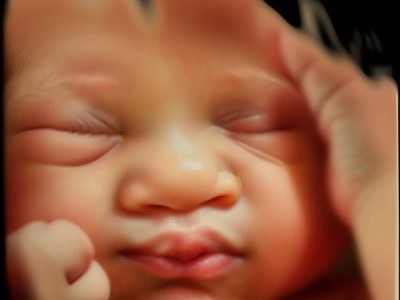

Las ecografías 5D con tecnología de hiperrealismo permiten obtener imágenes del bebé con un nivel de detalle muy superior al de las ecografías tradicionales. Gracias a esta técnica avanzada, podrás ver sus rasgos faciales, expresiones y movimientos con una nitidez increíble, creando una experiencia mucho más emocional y cercana durante el embarazo.

Para obtener estas imágenes tan precisas, utilizamos un ecógrafo de última generación que combina ultrasonido en tiempo real con un procesamiento avanzado de color y volumen. Durante la sesión, se aplica un gel sobre el abdomen materno y se desliza suavemente el transductor para captar cada ángulo del bebé. El sistema reconstruye esas imágenes en 3D y añade capas de luz, textura y profundidad, dando como resultado un efecto hiperrealista. Es un proceso seguro, indoloro y apto en cualquier etapa del embarazo.

Las Ecografías 5D e Hiperrealistas muestran al bebé con una claridad y precisión que permiten distinguir rasgos, gestos y volúmenes con gran realismo. Esta tecnología aporta una visión cercana y detallada, facilitando que las familias puedan observar de forma más natural cómo se va desarrollando su bebé.